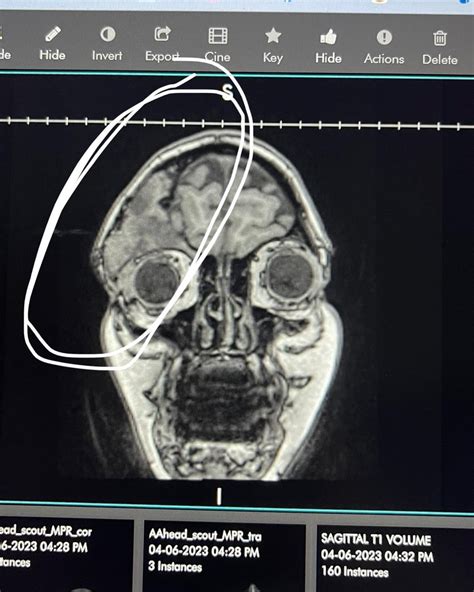

Magnetic Resonance Imaging (MRI)

MRI uses magnetic fields and radio waves to produce detailed images of the body's soft tissues. Unlike CT scans, MRI does not use ionizing radiation, making it a safer option for certain patients. MRI is particularly effective for imaging the brain, spinal cord, and joints, and is often used to diagnose conditions like multiple sclerosis, spinal cord injuries, and joint problems.

Neurology

In neurology, MRI and CT scans are commonly used to diagnose conditions affecting the brain and spinal cord. These techniques help in identifying strokes, tumors, and degenerative diseases like Alzheimer's and Parkinson's. Functional MRI (fMRI) is also used to study brain activity and function.